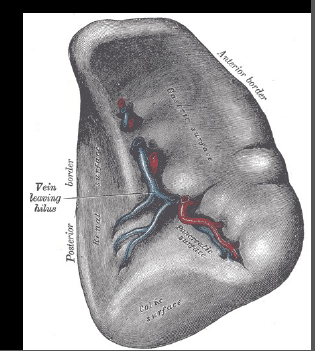

What surface is this?

inferior. notice the hilum